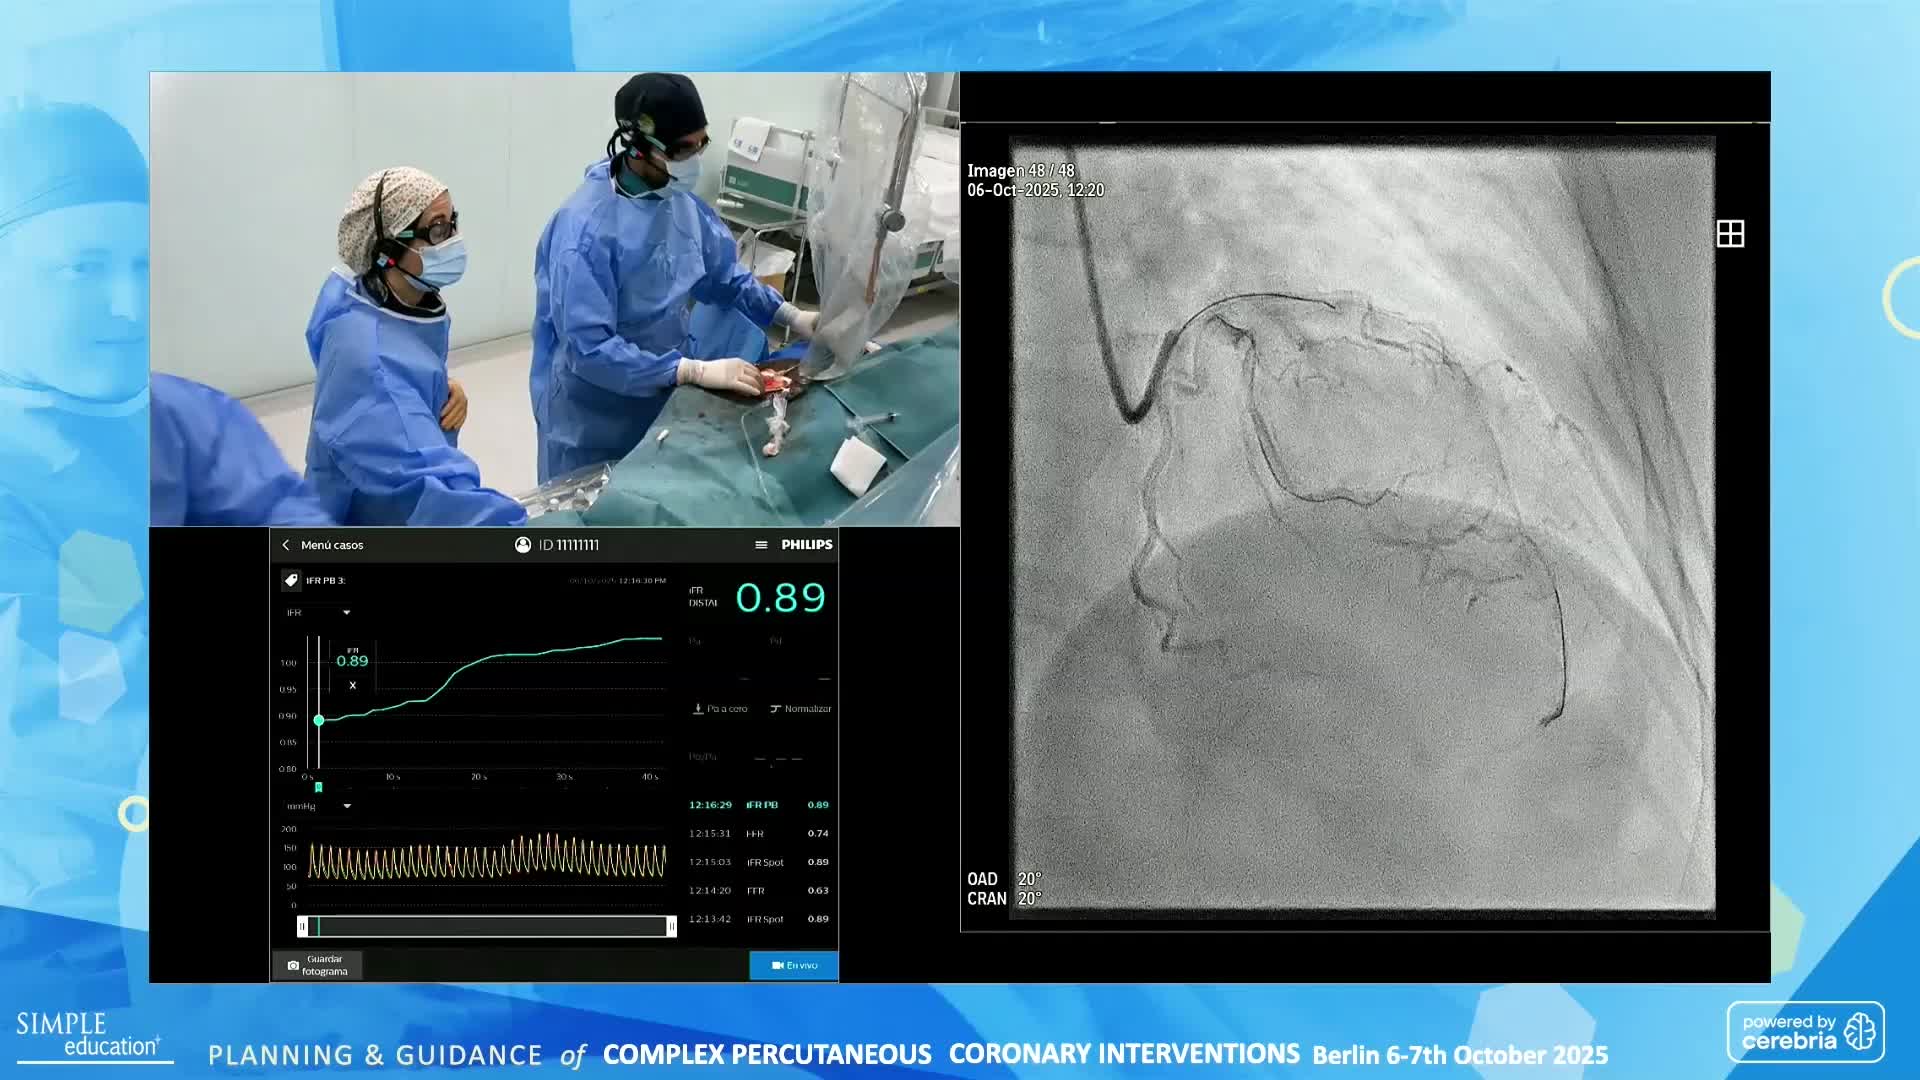

Planning and guidance of complex percutaneous coronary interventions - June 2023 Day One

Planning and guidance of complex percutaneous coronary interventions - June 2023 Day Two

Planning and guidance of complex percutaneous coronary interventions - October 2022 Day One

Planning and guidance of complex percutaneous coronary interventions - October 2022 Day 2

Planning and Guidance of Complex Percutaneous Coronary Interventions - May 2022 Day One

Planning and Guidance of Complex Percutaneous Coronary Interventions - May 2022 Day Two

Best practices and personalised medicine in complex PCI - Prof Javier Escaned

Essential steps for physiology-based PCI planning and guidance - Dr Allen Jeremias

Intracoronary guidance in acute coronary syndromes - Dr Hernan Mejia-Renteria

Functional assessment of coronary stenosis prior to TAVI - Prof Flavio Ribichini

Coronary Bifurcations: An Update on Diagnosis, PCI planning and Imaging and PhysiologyGuidance - Dr Dejan Milasinovic

Revascularisation in stable angina: a contemporary perspective - Dr Rasha Al-Lamee